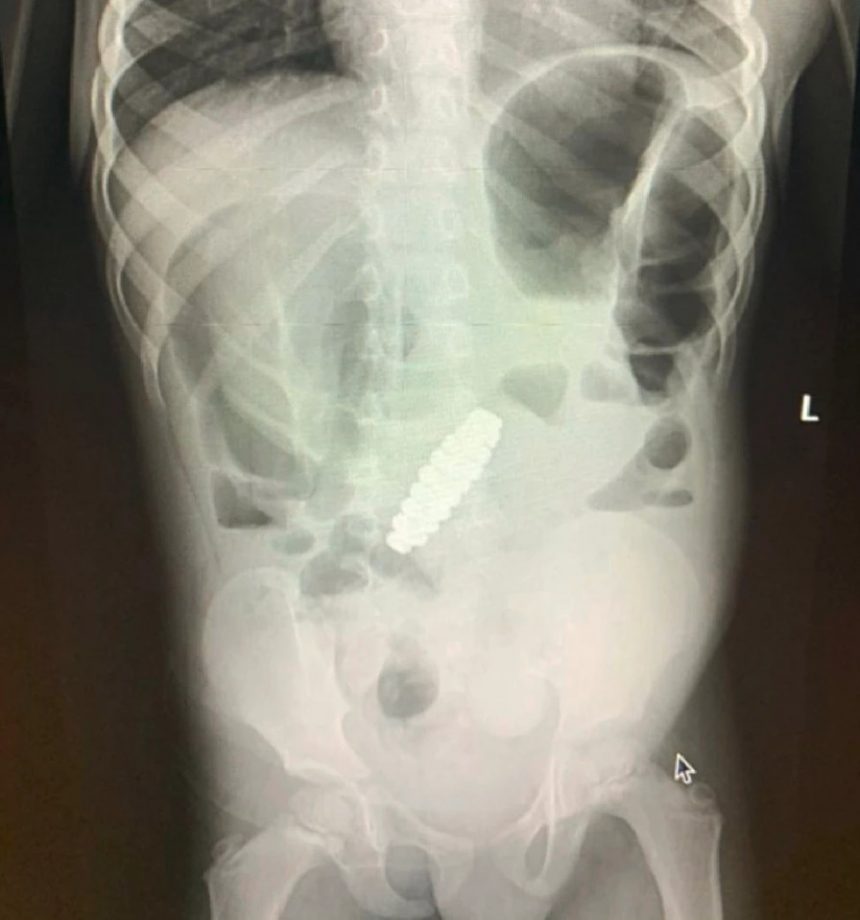

Пет дена по процедурата, лекарите направиле повторен ултразвук и откриле нараквица во стомакот на детето. Малото момче имало итна лапаротомија за да се отстрани предметот – за кој се покажало дека е нараквица составена од 18 магнетни зрнца во хексагонална форма. Нараквицата му ги попречувала цревата, како и ископала четири мали дупки во нив, кои лекарите можеле да ги поправат.